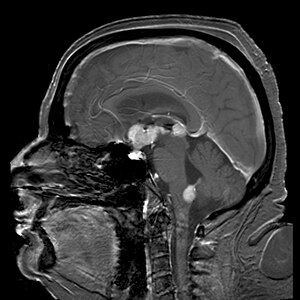

Brain magnetic resonance imaging showing primary central nervous system B-cell non-Hodgkin lymphoma of the sella turcica and hypothalamus, continuing to the tectum (intensely white areas in the middle).

MRI or contrast enhanced CT classically shows multiple ring-enhancing lesions in the deep white matter. The major differential diagnosis (based on imaging) is cerebral toxoplasmosis, which is also prevalent in AIDS patients and also presents with a ring-enhanced lesion, although toxoplasmosis generally presents with more lesions and the contrast enhancement is typically more pronounced. Imaging techniques cannot distinguish the two conditions with certainty, and cannot exclude other diagnoses. Thus, patients undergo a brain biopsy or vitreous biopsy, if there is intraocular involvement.[11]